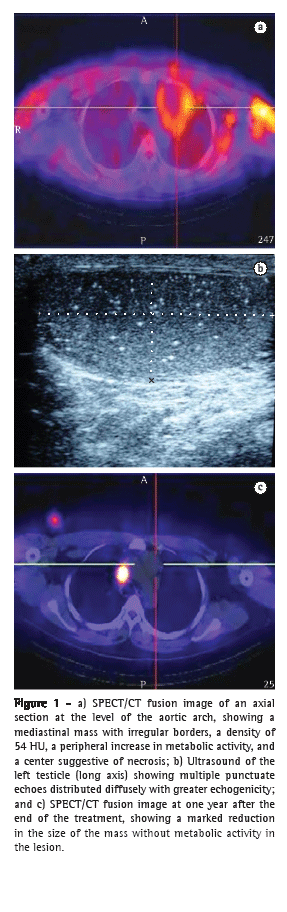

The patient was a 27-year-old, nonsmoking male construction worker with no family history of cancer. He sought treatment at our hospital, complaining of a two-month history of intermittent hemoptysis (≈30-60 mL/24 h), weight loss, and dyspnea (Modified Medical Research Council grade 2). The results of the physical examination, biochemical tests, and hematological studies were all normal. A chest X-ray taken at admission revealed an evident widening of the mediastinum. On the basis of these findings, we then quantified the serum tumor markers alpha fetoprotein and beta-human chorionic gonadotropin (Beta-hCG), obtaining values of 2.59 ng/mL (reference values, 0.67-3.2 ng/mL) and 13.5 mIU/mL (reference value for males, < 2.5 mIU/mL), respectively. Single-photon emission CT (SPECT) scans, in conjunction with standard CT scans, revealed an irregular mass (approximately 8 × 8 cm in size) in the anterior mediastinum, varying from 40 to 54 HU in density (Figure 1a).

Bronchoscopy revealed hyperemic, edematous bronchial mucosa with hemorrhagic stippling and traces of blood in the bilateral basal segments, although there was no active bleeding. There was no invasion of the lumen or ulceration of the bronchial wall. A CT-guided biopsy of the mediastinal mass was performed. The histopathological study of the biopsy sample showed necrosis, cell detritus, and large pleomorphic cells, in which the cytoplasms were clear, the nuclei contained coarse chromatin, and the nucleoli were evident, with a neoplastic appearance. Immunohistochemical staining showed a positive response for cytokeratin AE1/AE3, chorionic gonadotropin hormone, and alpha fetoprotein, although the responses to synaptophysin and the leukocyte antigen, which are common in neoplastic cells, were negative. The anatomopathological diagnosis was of a seminomatous GCT, a diagnosis that was underscored by the findings of normal serum alpha fetoprotein and moderately elevated serum Beta-hCG. To evaluate the extent of the tumor, we carried out SPECT/CT scans of the abdominal cavity, pelvic cavity, brain, and liver but failed to identify any abnormalities. The TM was identified through ultrasound (Figure 1b). Vascularity was found to be adequate in both testicles. The patient received six cycles of chemotherapy with cisplatin, etoposide, and bleomycin. After the treatment, the hemoptysis resolved. In addition, post-treatment SPECT/CT fusion imaging showed a reduction in the size of the lesion and the absence of any metabolic activity within the lesion, a condition that persisted at one year after the end of the treatment (Figure 1c).